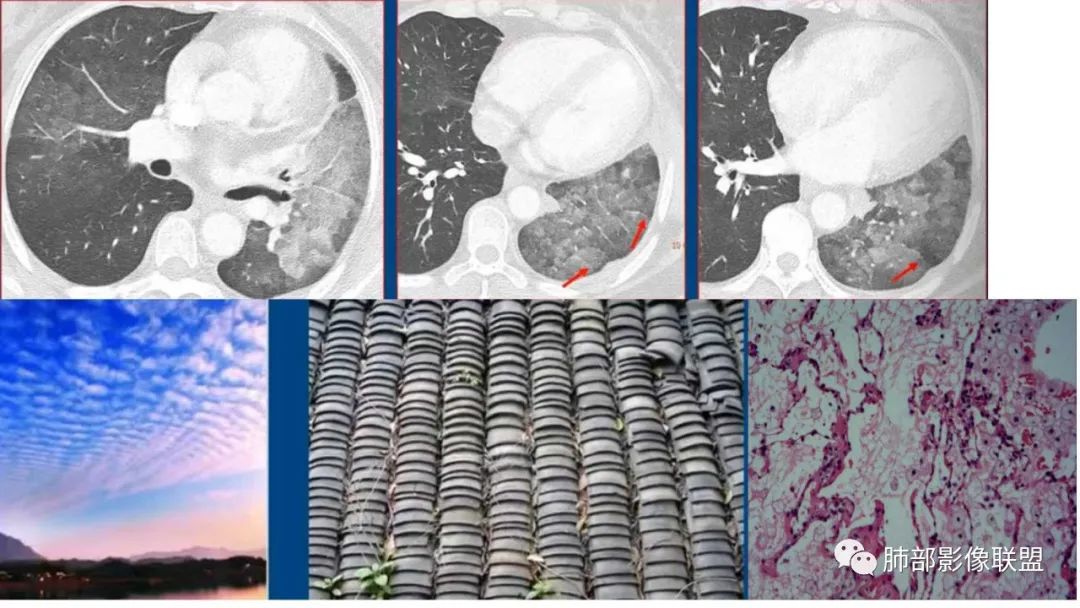

3、重力作用,叠瓦征。近叶间裂因重力效应,呈膨隆改变。

5、支气管粗细不均,呈“枯树枝征”,但与肺炎这一点鉴别不具有统计学差异。可发生支气管扩张

6、空腔形成,部分蜂窝状改变。

9.粘液腺癌的变化规律:结节缓慢发展而来,向周围播散形成斑片后可快速进展,有时支气管镜后或粘液排出后局部可形成好转的假象。病灶可沿肺泡和支气管播散。